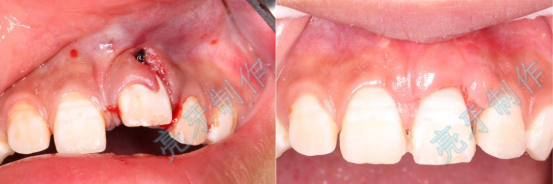

病例二:外伤导致上牙槽骨骨折,而且上下两颗门牙脱位;通过治疗,上下两颗门牙均恢复原来位置,而且和之前一样结实。